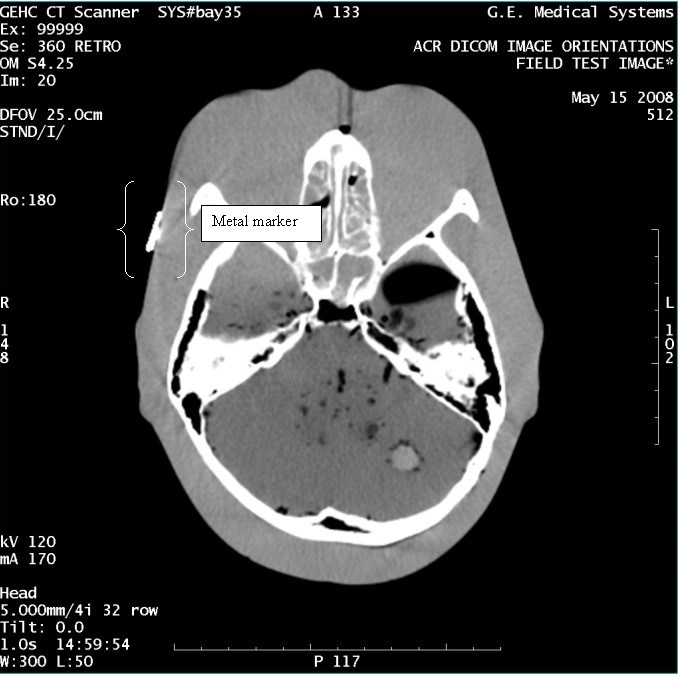

- With the support of the site personnel, examine the images sent

to the Review Station (i.e., 12 series, each with 1 image) and compare

their orientation to the images in this document.

- Each image contains a metal marker on the phantom's right cheek.

- Each image in this document contains a description of the expected

orientation of the metal marker (i.e. to prove Left and Right) as

well as the Posterior and Anterior orientation description.note:

The sample images included in this document use “R”, “L”, “P”, and “A” for “Right”, “Left”, “Posterior” and “Anterior” orientation. The Hospital Review Station may use a different style of annotation. The style used is not relevant to this procedure.

Figure 13. Exam 99999, Series 360